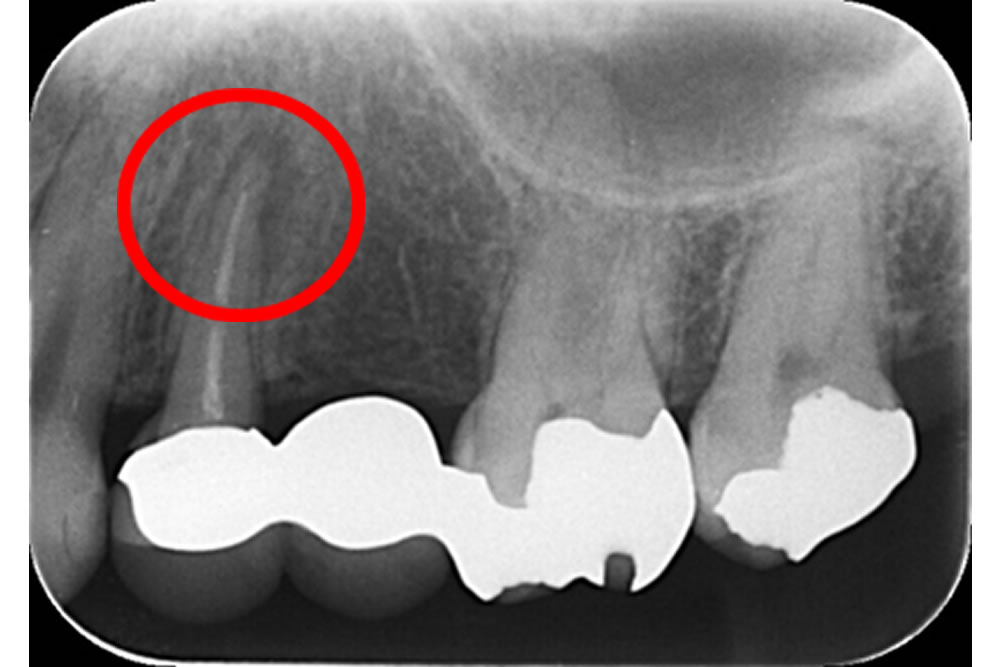

こちらの患者さまは他院で入れたブリッジの土台の歯(4番目の歯)の歯茎が腫れてきてしまったため、治療を行うことになりました。